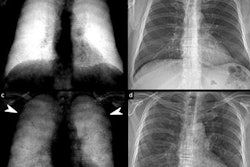

"Interpretable AI" heatmaps from real-time implementation indicating features used for AI model prediction. COVID-19 negative and positive chest radiographs (gray) and representative heatmaps (colored) from real-time implementation output are shown. Features of importance for model predictions are represented by the red end of the heatmap spectrum, and blue represents features of least importance. Representative images with both high and low diagnostic scores are provided. Black boxes were added for the purpose of blocking any potential patient information for publication purposes. Image courtesy of Radiology: Artificial Intelligence.

"Interpretable AI" heatmaps from real-time implementation indicating features used for AI model prediction. COVID-19 negative and positive chest radiographs (gray) and representative heatmaps (colored) from real-time implementation output are shown. Features of importance for model predictions are represented by the red end of the heatmap spectrum, and blue represents features of least importance. Representative images with both high and low diagnostic scores are provided. Black boxes were added for the purpose of blocking any potential patient information for publication purposes. Image courtesy of Radiology: Artificial Intelligence.Next, in collaboration with Epic Cognitive Computing in Verona, WI, the researchers integrated the AI model into Epic at 12 University of Minnesota hospitals as a clinical decision-support system.